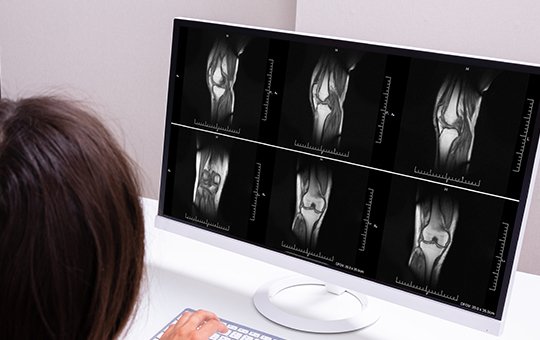

베스트장내과는 골밀도 검사와 상태 평가를 통해

개인별 골절 위험도를 정확히 진단합니다.

베스트장내과 골밀도 검사와 건강 상태 평가를 통해

개인별 골절 위험도에 맞는 치료를 시행합니다.